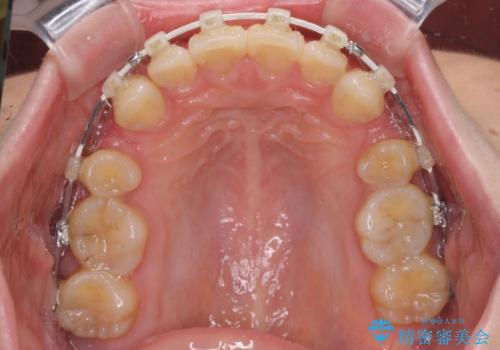

上顎前突 目立たないワイヤー装置での抜歯矯正

- 矯正装置

- 審美装置

- 口元の突出感改善を希望して来院された患者様です。

口元を積極的に引っ込めるために、上下左右の小臼歯計4本を抜歯することとしました。

咬み合わせが深いため、咬み合わせの高さを向上させながら口元を下げることとしました。

左右ともに下顎に対して上顎歯列が前方位にある上顎前突であったので、上顎歯列全体を後方に移動させることで上下咬み合わせを改善し、その上で抜歯矯正により口元の突出感を改善させていきました。